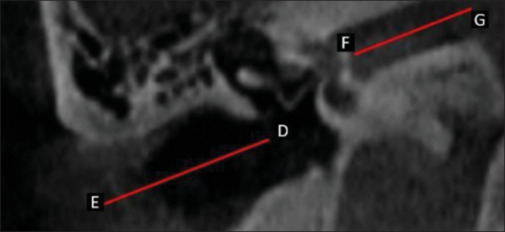

Introduction: The tympanic cavity contains three tiny bones, the malleus, incus, and stapes, which have a fundamental role in the transmission of sound. Recent research emphasizes the use of CBCT for the anatomic study of the temporal bone. The information about middle ear anatomy on CBCT scans is meager; hence, this retrospective study was conducted to identify and determine the various morphometrical parameters of the malleus using CBCT which can be helpful during reconstructive procedures for the otologic surgeon.

Materials and methods: The retrospective study was performed on 200 subjects (101 M and 99 F) in the Department of Oral and Maxillofacial Radiology. CBCT images of 200 subjects were studied in all planes to identify ossicular chain and the malleus to investigate the morphometric parameters in Indian Subjects.

Result: The average of morphometric parameters shows that the mean length of the malleus is 7.2 mm, the mean width of the head of the malleus is 3.02 mm, length of superior semicircular canal is 4.90 mm, and length of external auditory canal is 19.15 mm in Navi Mumbai population.